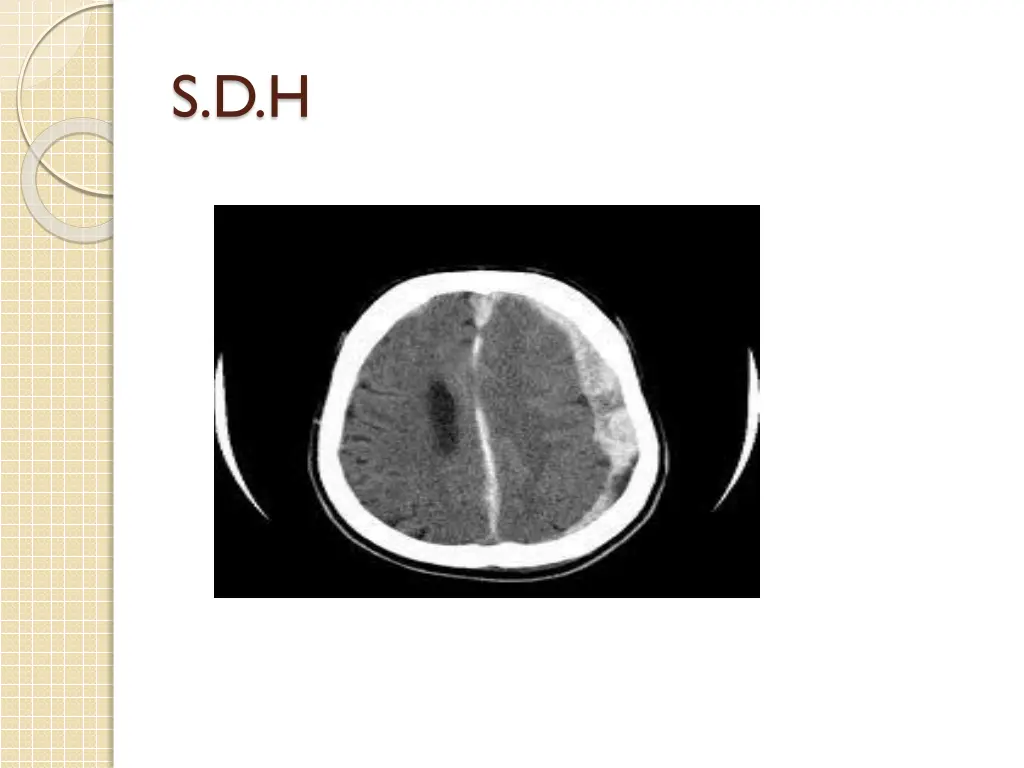

2- focal inj.:defined as visible damage that is generally limited to a well circumscribed region; e.g contusions(coup &countercoup),SDH,EDH,S.A.H,ICH,IVH Occur in half of all pat. With severe brain inj., ,and 2/3 of brain inj.related death.

S.D.H : associated contusion and brain laceration result from contact or acceleration effect or result from torn cortical vessels especially in trivial head trauma in old age patients